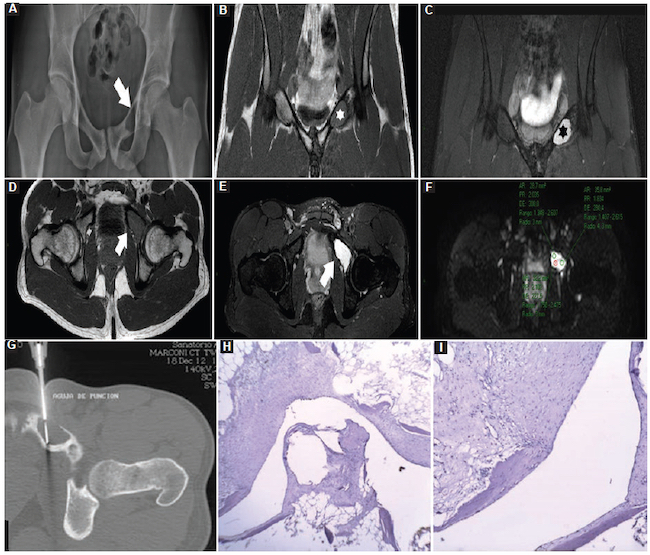

Quiste óseo simple: fueron nueve casos, con un valor medio de CDA de 2,02 ± 0,54 × 10−3 mm2/s (1,30-2,70) (Fig. 11), de los cuales fueron dos en los miembros superiores, seis en los miembros inferiores y uno en la pelvis.

Para las biopsias se utilizaron agujas dedicadas para cada tejido. Cuando las lesiones fueron de partes blandas se procedió con guía ecográfica con un equipo Mindray Resona 7 (Mindray Headquarter, Shenzhen, República Popular de China), con transductor de alta frecuencia, y se utilizaron agujas de corte tipo Tru-Cut de 14 o 16 G con una longitud de 10 cm (dependiendo del tamaño de la lesión), montadas en una pistola de disparo automático a doble armamento (Fig. 2). Cuando las lesiones fueron óseas se procedió con guía tomográfica con un equipo Siemens Somatom Sensation de 64 Canales (Alemania, Erlangen) y se utilizaron agujas de punción ósea para médula ósea de 11 × 4 G (Fig. 3).

Para ambos procedimientos se utilizaron campo estéril, guantes estériles, jeringa de 5 ml tipo Terumo y aguja de 21 G para la instilación de anestésico local (lidocaína al 2%, 5 ml). Una vez adquirida la muestra, se colocó en un frasco estéril con formol al 10%. Cada frasco fue correctamente rotulado con la fecha de la biopsia y la correspondiente hoja de identificación (datos del paciente, sitio de punción, cantidad de muestras y diagnóstico presuntivo por imágenes).

Las muestras fueron analizadas por el anatomopatólogo mediante técnica de tinción simple con hematoxilina-eosina para realizar el diagnóstico de patología benigna o maligna (Fig. 4). Se informó el tipo de patología y se clasificaron las lesiones malignas determinando también el grado de infiltración.